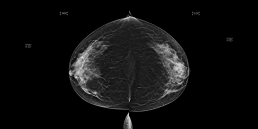

Sur la mammographie de dépistage de cette patiente, MammoScreen repère plusieurs lésions avec un score jaune de 5 (indéterminé).

Les calcifications repérées dans le sein gauche en CC sont bénignes.

Cependant la masse de score 5 du sein droit détectée à la fois sur la CC et la MLO correspond à un petit cancer infiltrant. Grâce à la tomosynthèse, MammoScreen a pu bien repérer cette lésion, notamment grâce à la coupe numéro 16 de la CC.

Grâce au score jaune, MammoScreen peut attirer l’attention sur des lésions subtiles qui peuvent dans certains cas être malignes.